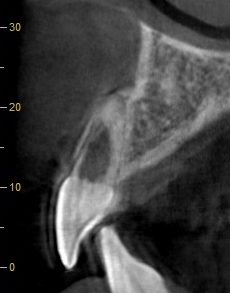

本症例において、主訴ではない左上顎中切歯には「歯根の内部吸収」を認めました。レントゲン撮影時に偶発的に見つかった所見です。

歯根吸収は進行して歯質が菲薄化しており、いつ折れてもおかしくない状況でした。内部吸収は根管治療で進行を止められる可能性がありますが、失われた歯質は回復しません。残存歯質量の少なさから、保存的治療は困難と判断し、患者様にご説明いたしました。 (※永久歯の歯根吸収は原因不明なことも多いですが、お話を伺う限り、過去の外傷を起因とするものと推察されました。)